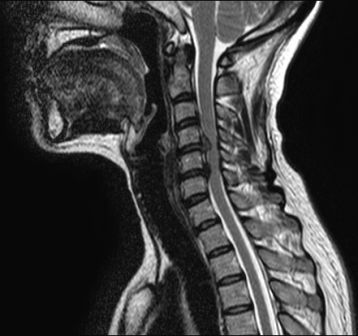

Magnetic Resonance Imaging has become a routine test in the evaluation of musculoskeletal conditions. Most patients with neck, back, knee or shoulder pain will improve with conservative management. MRI often shows pathology (aka that something is wrong) that may have no relationship to the patient’s symptoms. Tests have shown that young and middle-aged people with NO symptoms 30-40% of the time have changes in their disks. The MRI can give confusing information that may not identify the source of pain.

To optimize healing, I do a thorough history and physical exam. Certainly, if there are “red alarms” like infection or acute disc herniation or cauda equina syndrome, then an MRI is warranted. If conservative therapy does not help resolve the problem in 4 to 6 weeks, then an MRI may help also. We physicians are trained to not obtain tests that won’t help the diagnosis or plan of care. MRI is not indicated if the result will not alter treatment. Muscle stretching and strengthening are the cornerstones of rehabilitation. That requires the patient be motivated and engaged in therapy.